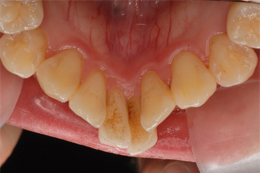

マウスピース矯正装置にて上下顎の矯正を行いました。

足りないスペースは側方への歯列拡大とIPR(歯の間の削り込み)を行い矯正しました。